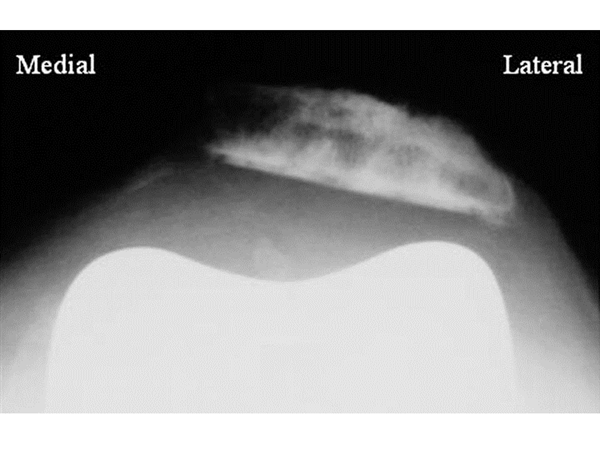

19

Q

This patient has undergone single knee TKA. Post operatively, she experience pain in her knees. Plain radiograph is done and is shown.

1. Describe the plain radiograph.

2. What is the problem.

3. How to avoid this problem intra-operatively.

4. How to manage this problem intra-operatively.

5. How to manage this problem post-operatively.

A

1. Skyline/tangential view of the knee with anterior surface of femoral prosthesis and patella in view.

Unable to comment on femoral prosthesis.

Patella tilt with lateralisation noted, not within the trochlear groove, articular surface showed evidence of pateloplasty.

1. Patella maltracking.

2. Avoid- Intra-operative

DO NOT

• internally rotate femoral and tibial component.

• medialise femoral and tibial component.

• place laterally the patellar component.

INSTEAD SHOULD DO

• externally rotate femoral 3 degrees

• keep femoral component slightly lateral

• neutral placement of tibial component, centered at medial ⅓rd of tibial tubercle

• place medially or at neutral the patellar component.

1. Tackle - Intra-operative

• release tourniquet to check for maltracking.

• if still present, perform lateral release (manipulate soft tissue)

How well did you know this?